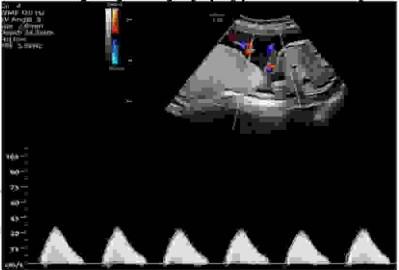

Monitorowanie echokardiograficzne płodu kątem zaburzeń przewodzenia jest rekomendowane w przypadku obecności przeciwciał anty-Ro/SSA i anty-La/SSB u matki (np. w toczniu układowym). W czasie monitorowania ocenia się czas przewodzenia przedsionkowo-komorowego. Dzięki wiedzy o odzwierciedleniu zjawisk elektrofizjologicznych przez zjawiska mechaniczne zachodzące podczas cyklu pracy serca dokonuje się następującego pomiaru: